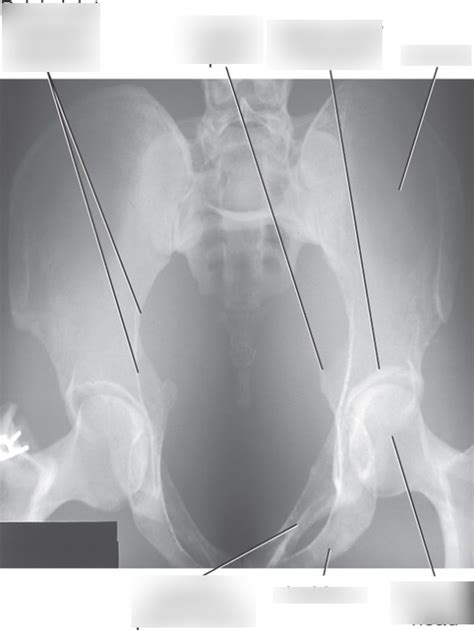

Key Anatomical Structures to Identify:

• Sacroiliac (SI) Joints: These joints connect the sacrum to the iliac bones. On the AP Axial view, you should be able to clearly visualize the SI joints and assess their alignment and joint space.

• Symphysis Pubis: This is the joint where the two pubic bones meet in the front of the pelvis. Look for any widening or displacement of the symphysis pubis, which could indicate a pelvic fracture or instability.

• Pelvic Inlet: This is the opening into the true pelvis. The AP Axial view is designed to provide a clear view of the pelvic inlet, allowing you to assess its shape and symmetry. Any distortion or asymmetry could suggest a fracture or dislocation.

• Iliac Crests, Ischial Spines, and Pubic Rami: These bony landmarks should be clearly visible and free from any obvious fractures or deformities.

• Sacrum and Coccyx: Although the primary focus is on the pelvic ring, it’s also important to assess the sacrum and coccyx for any abnormalities.